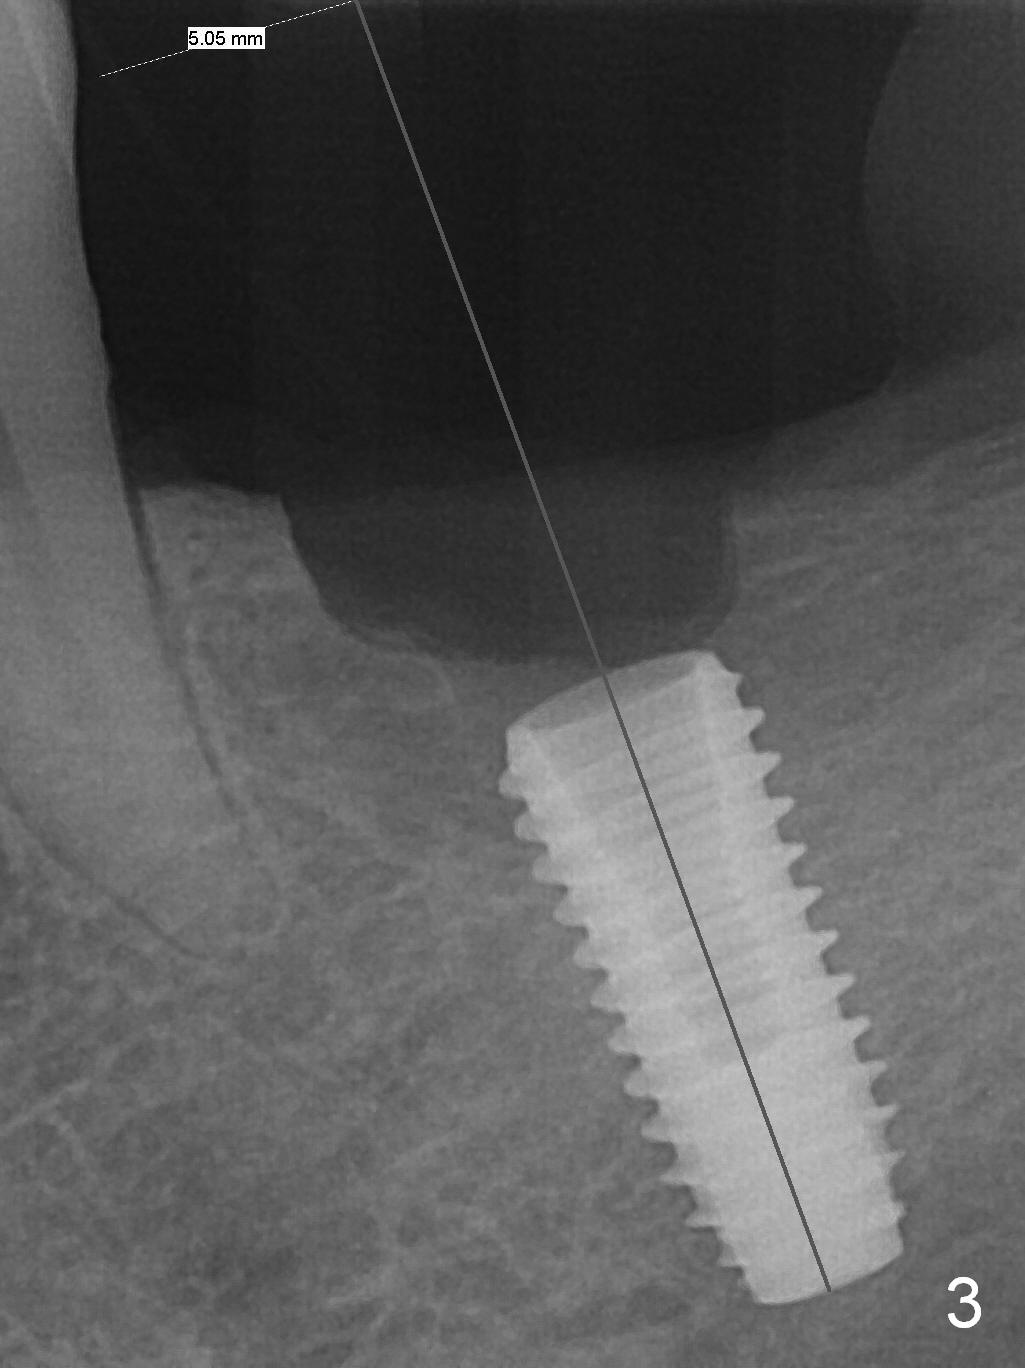

As indicated by CBCT, the ridge at the site of #19 is pointed (Fig.1). After regional ridge reduction (Fig.2) and use of 2 mm pilot drill for 8.5 mm, the depth is actually ~ 10 mm. After sequential osteotomy until 4.3x10 mm drill, the osteotomy is in fact 11.5 mm deep; a 5x11.5 mm implant is placed with <35 Ncm (Fig.3). Panoramic X-ray shows the implant close to the superior border of the Inferior Alveolar Canal (Fig.4 red dashed line). The ridge looks wider and more bulging (*) when a 6.5x5.5(5) mm abutment, allograft/Osteogen and Osteotape (GBR) are placed (Fig.5 (lingual) and 6 (buccal)). Periodontal dressing is then applied. There is no postop paresthesia. The abutment dislodges 3 weeks postop. A healing abutment is placed (6.5x4 mm). The patient returns for restoration 4 months postop; bone density appears to increase around the implant (Fig.7 arrowheads). When a 7.5x5(4) mm abutment is placed, there is transient pressure on the gingiva (blanching). The mesial gingival trough is formed by Diode laser prior to impression.